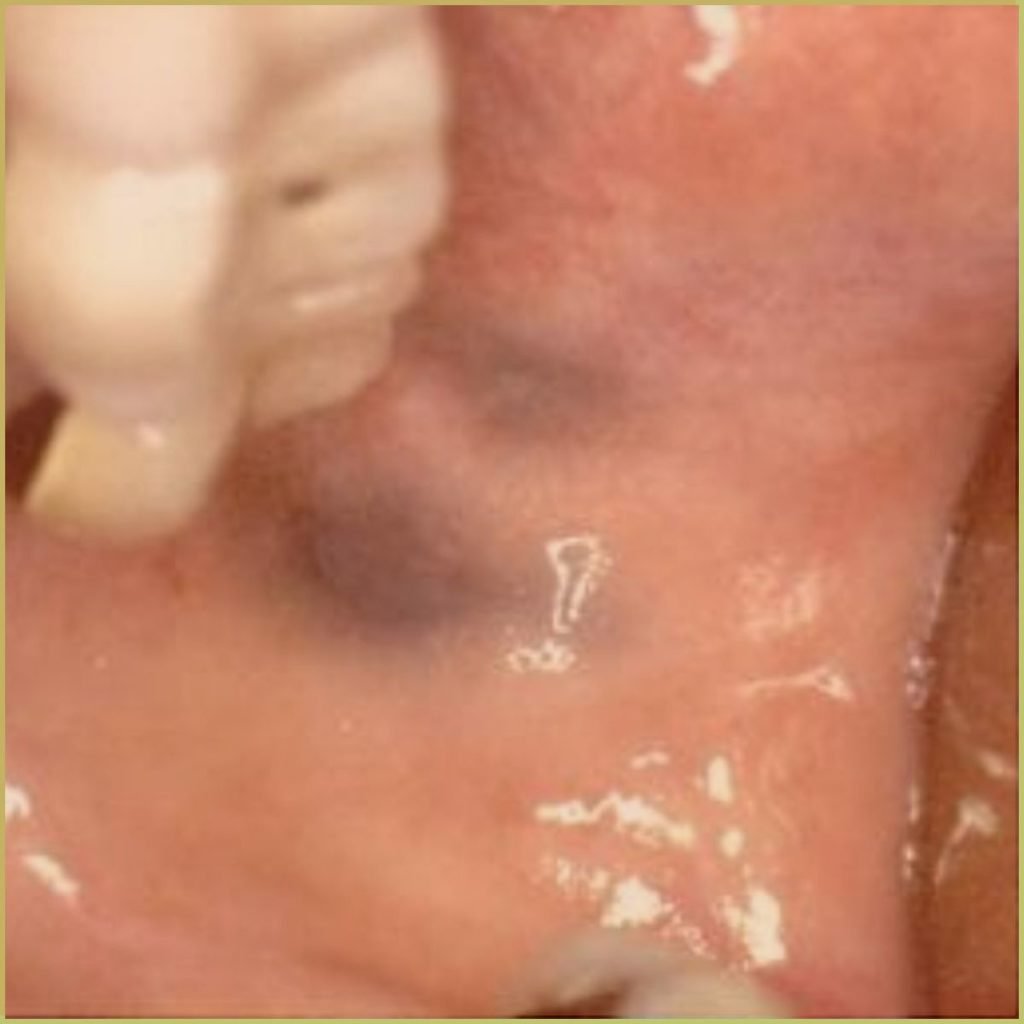

AMALGAM TATTOO

Amalgam Tattoo refers to the discoloration seen in oral tissues where dental amalgam has been deposited. The common clinical presentation includes:

- Well differentiated gray, blue or black focal macule.

- Asymptomatic lesions with no indication of associated inflammation.

- May be visible radiographically.